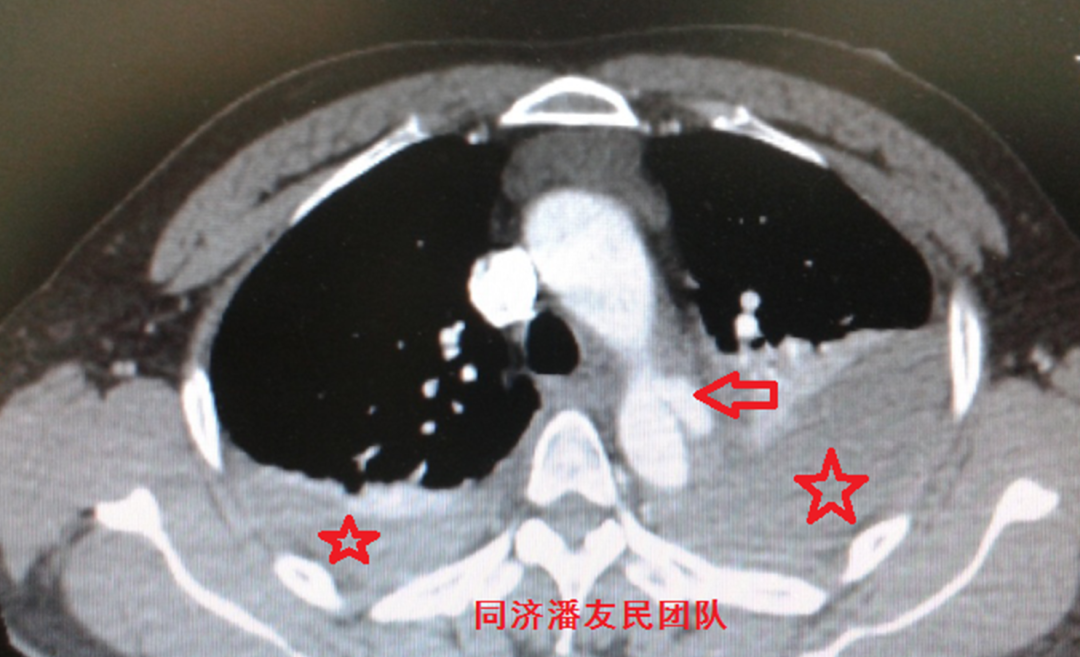

图1:胸部平扫CT显示降主动脉管腔内可见内膜片(红箭头所示),考虑主动脉夹层。同时显示纵隔血肿(红星号)及左侧少量胸腔积液(白箭头所示)。

入院后,胸腹主动脉CTA将主动脉及胸腹腔脏器一起进行全面评估。与图1平扫CT层面对应,图2显示降主动脉夹层。

图2:与上图1平扫CT层面相对应,红箭头显示降主动脉夹层,红星号显示纵隔血肿,白箭头显示胸腔积液。